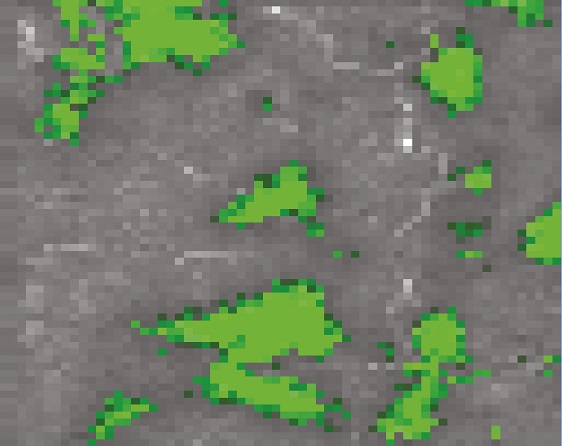

En digitalt producerad bild som illustrerar hur biokemiska förändringar i bukspottkörtelvävnaden kan studeras med forskarnas metod utan att behöva färga in vävnaden. I grönt syns lokaliseringen av förhöjda nivåer av sk. beta-sheet proteiner som är ett tecken på utveckling av typ 2 diabetes.